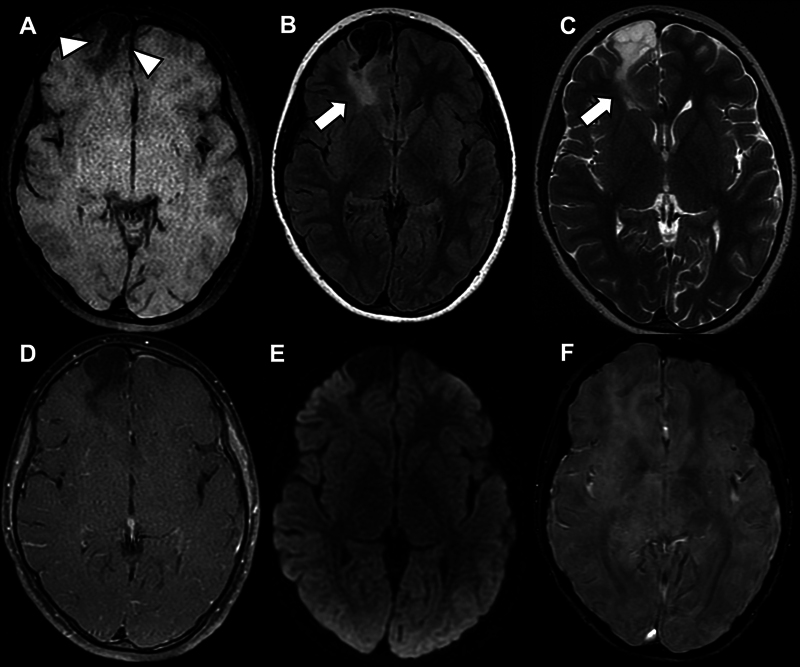

Angiocentric glioma in refractory epilepsy: when to suspect?

难治性癫痫的血管中心性胶质瘤:何时怀疑?